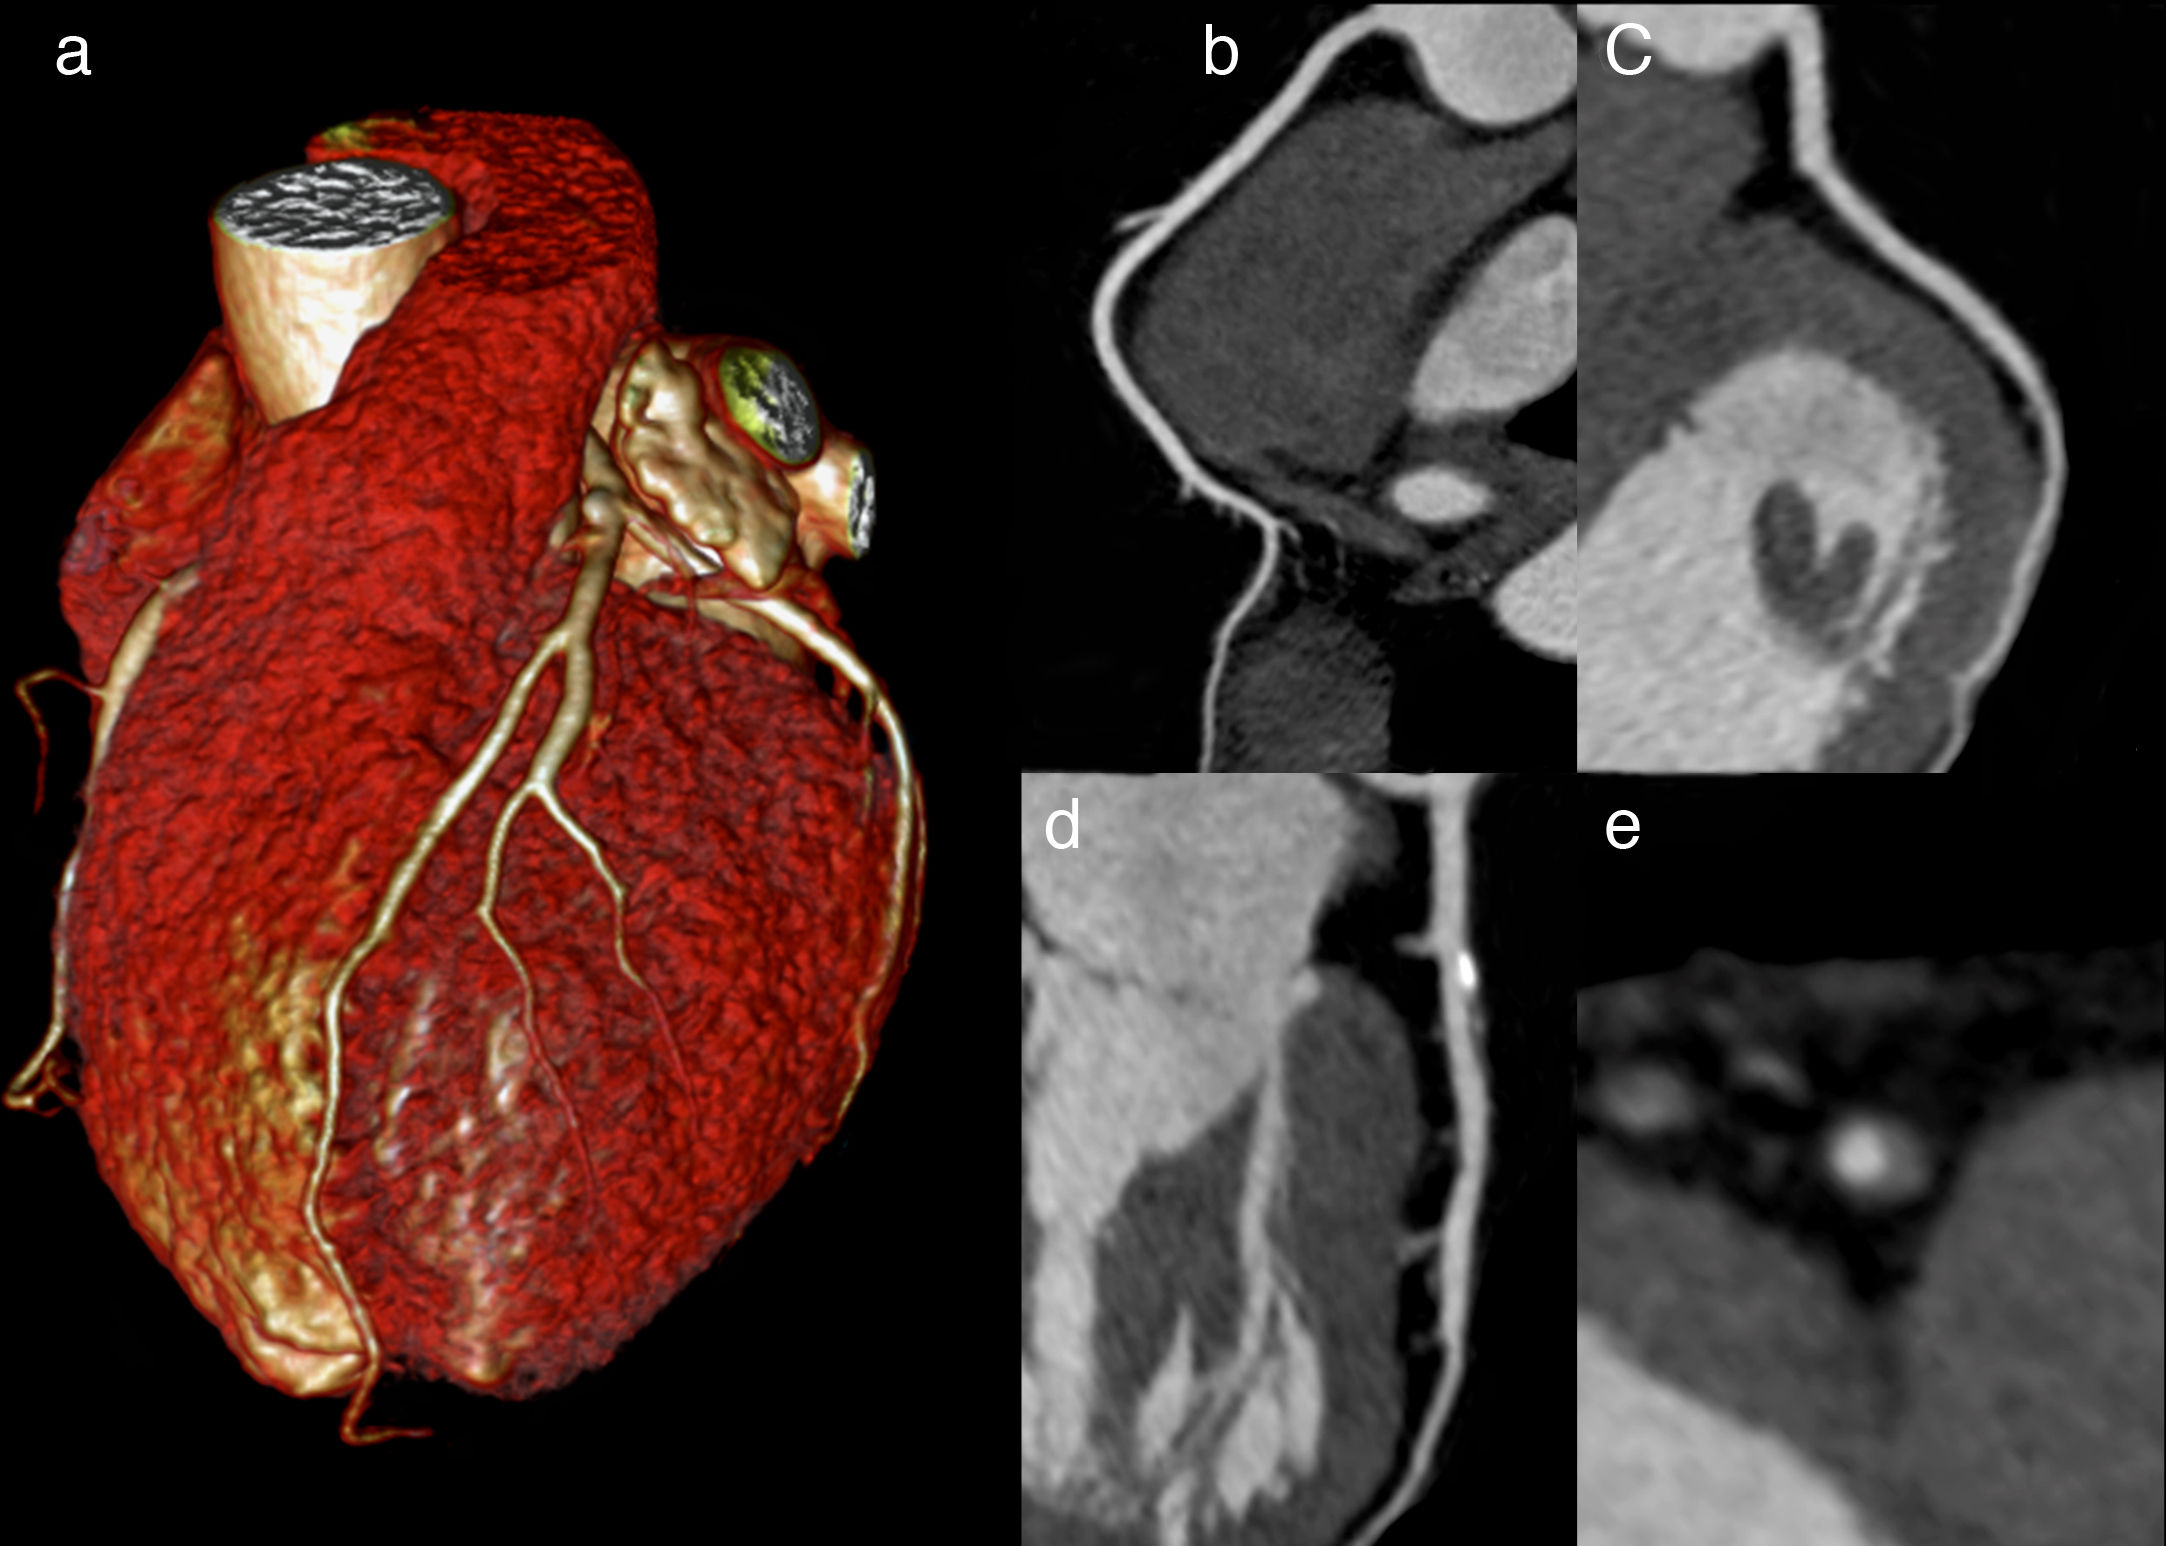

Tratamiento guiado por angiografía coronaria por TC de pacientes con angina de pecho estable: resultados a 10 años

El tratamiento guiado por angiografíca coronaria por tomografía computada (ACTC) de los pacientes con dolor torácico estable se asoció con una reducción sostenida de la muerte por enfermedad coronaria o infarto de miocardio no mortal. La identificación de la aterosclerosis coronaria mediante ACTC mejora la prevención de la enfermedad cardiovascular a largo plazo en pacientes con dolor torácico estable. The Lancet, 25 de enero de 2025.